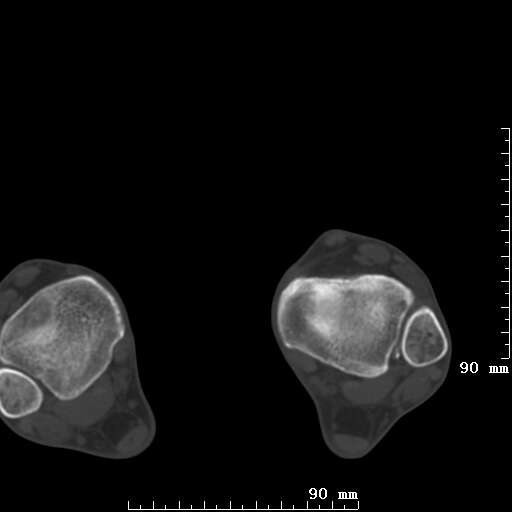

标题: CT19820:外伤一天,如何定性.男27Y [打印本页]

标题: CT19820:外伤一天,如何定性.男27Y

排除下创伤性关节炎吧,距骨有些囊变和硬化,周围韧带软组织有些机化、钙化。不是很像距骨无菌性坏死,感觉在关节面上的多,而不是距骨里面。

未见骨折及脱位像。距骨像是剥脱性软骨炎

支持!(踝关节距骨表面囊变和硬化 缺损)

距骨剥脱性软骨炎可能;踝关节创伤性关节炎?

未见明确新鲜骨折改变,距骨剥脱性软骨炎或踝关节创伤性关节炎可能。